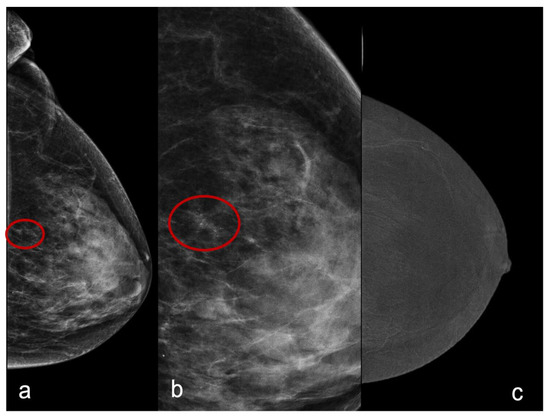

For the first analysis, we considered the unenhanced pattern (score 0) and minimally enhanced pattern (score 1) predictive of benignity and the moderately enhanced pattern (score 2) and markedly enhanced pattern (score 3) predictive of malignancy (Figure 1 and Figure 2).

Figure 1.

A craniocaudal mammography image of a 56-year-old with a cluster of microcalcifications (a). In (b), we can appreciate the magnification of the cluster of microcalcifications. There is no evidence of enhancement (score 0) in the CESM subtracted recombined image (c). Histology was fibrocystic disease.